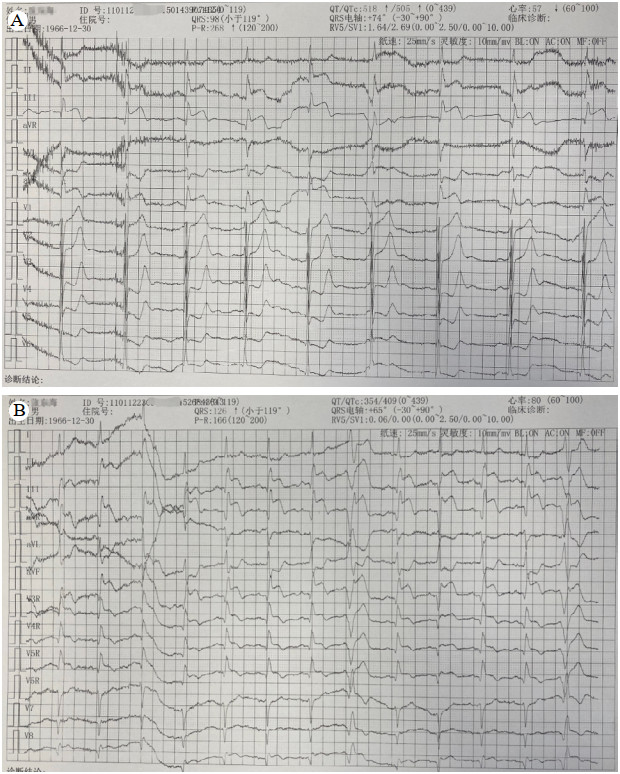

1 病例资料患者56岁男性,因“胸闷、大汗、左侧肢体活动障碍3 h”于2023-09-12入院。入院当日13:20患者突发胸闷大汗、左侧肢体完全不能动弹,15:12至急诊时神志不清。患者既往患高血压病10年,否认烟酒嗜好,否认家族遗传性疾病史。查体:血压120/80 mmHg(1 mmHg=0.133 kPa),神志模糊,两肺无啰音,心率70次/min,心律齐,无杂音,四肢肌力检查不配合,左侧肢体肌张力低,右侧肢体肌张力正常,左侧巴氏征阳性,右侧巴氏征阴性。随机血糖8.34 mmol/L,18导联心电图:窦律,下壁、右室导联ST明显抬高(图 1A、B),心肌酶的肌钙蛋白I:0.038 ng/mL(参考值0~0.034 ng/mL),头颅CT示无脑出血,可见右侧颈内动脉末端高密度征(图 2),提示颈内动脉远端存在血栓。

| 注:A为下壁导联ST段抬高0.3 mV;B为右胸导联ST抬高0.15 mV 图 1 入院18导联心电图 |